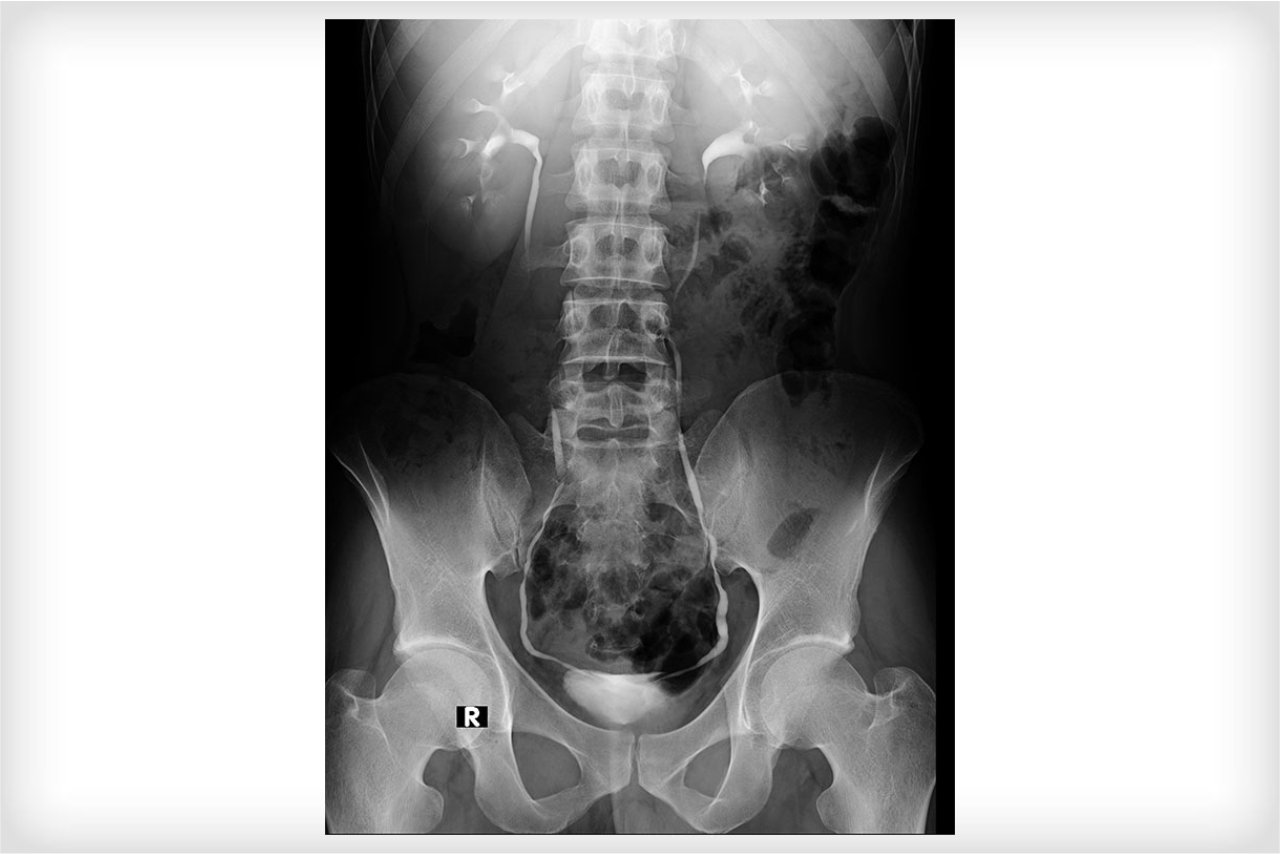

For the first time in Kutch, we have installed a High Tech. State of the Art GE Lunar DPX NT (Bone Densitometry System) for the assessment of Osteoporosis and Fat analysis.

Bone density scanning, also called dual-energy x-ray absorptiometry (DEXA) or bone densitometry, is an advanced form of x-ray technology that is used to measure bone loss. DEXA is today's Gold standard for measuring bone mineral density (BMD)

Our Lunar DPX NT also provides Body Composition scans with exceptionally precise and accurate data on lean tissue mass and fat tissue mass to diagnose obesity.